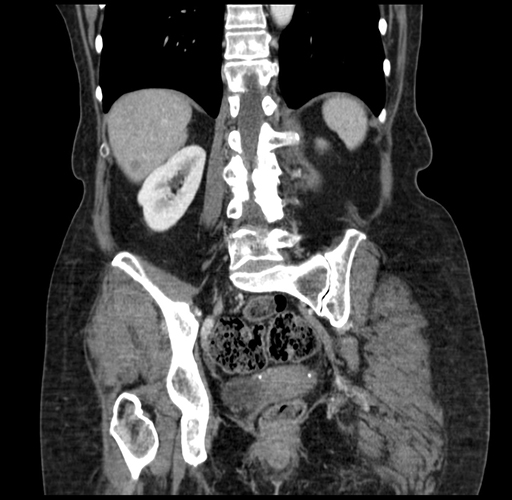

Pre-Chemo: Coronal Venous

Coronal Venous